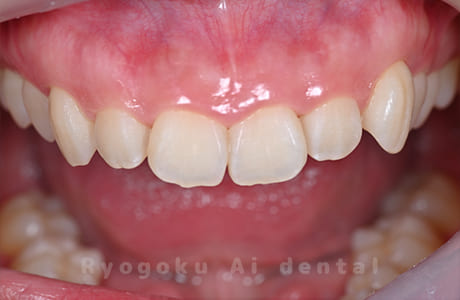

Case01

- 原因

- ガミースマイル

- 治療回数

- 1回

- 治療期間

- 術後治癒も含めて約1か月

- 治療内容

- ガミースマイル改善治療

- 治療費用

- 121,000円

(1ブロックあたり、6前歯部分)

笑った時に歯茎が見えてしまうガミースマイルを改善したいとのことでご来院された患者様です。術後も大変満足していただきました。